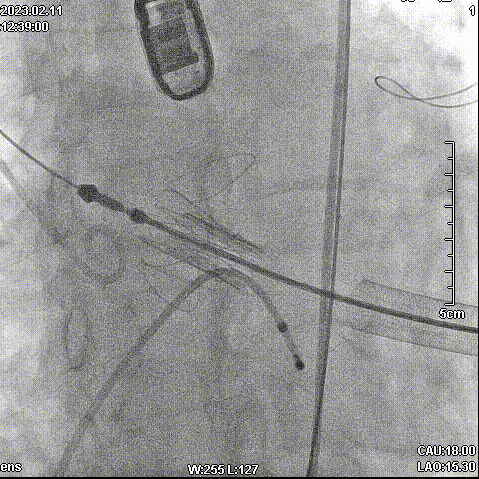

手术步骤

拔除股动脉血管鞘,缝合股动脉。手术顺利结束。